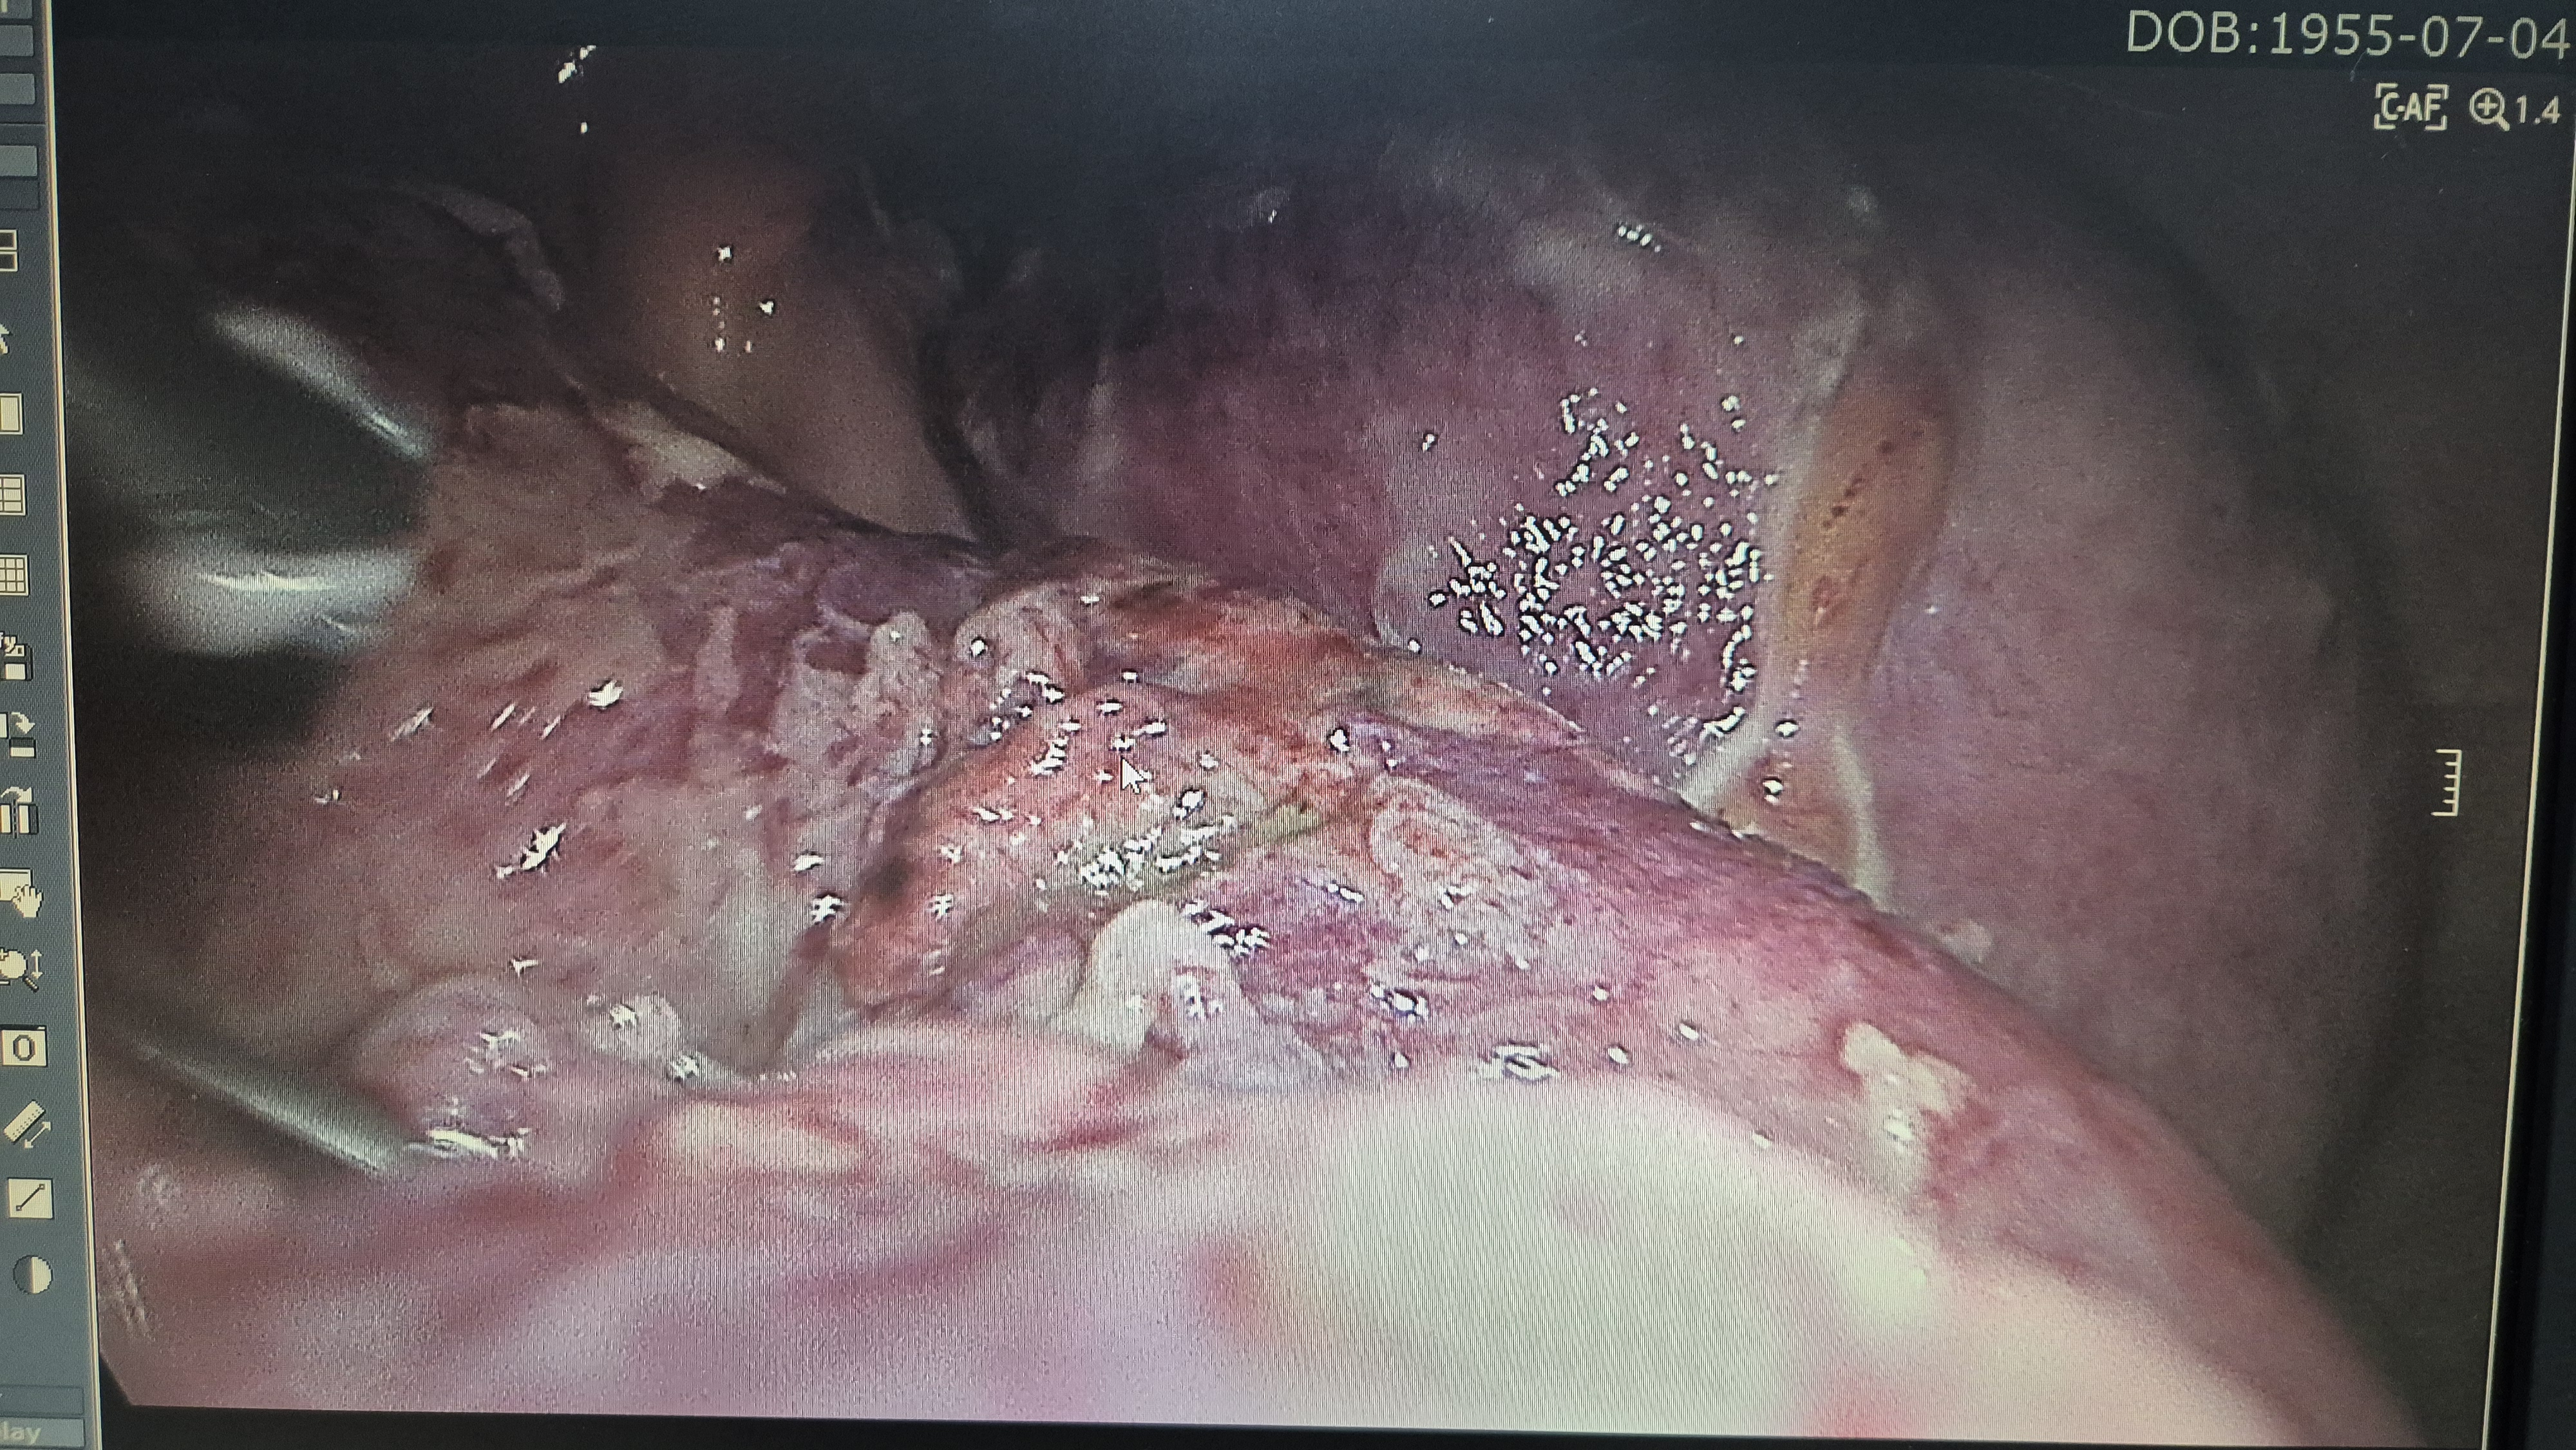

복강내 장내용물로 오염되어 있고,

소장천공을 확인.

봉합을 시행.